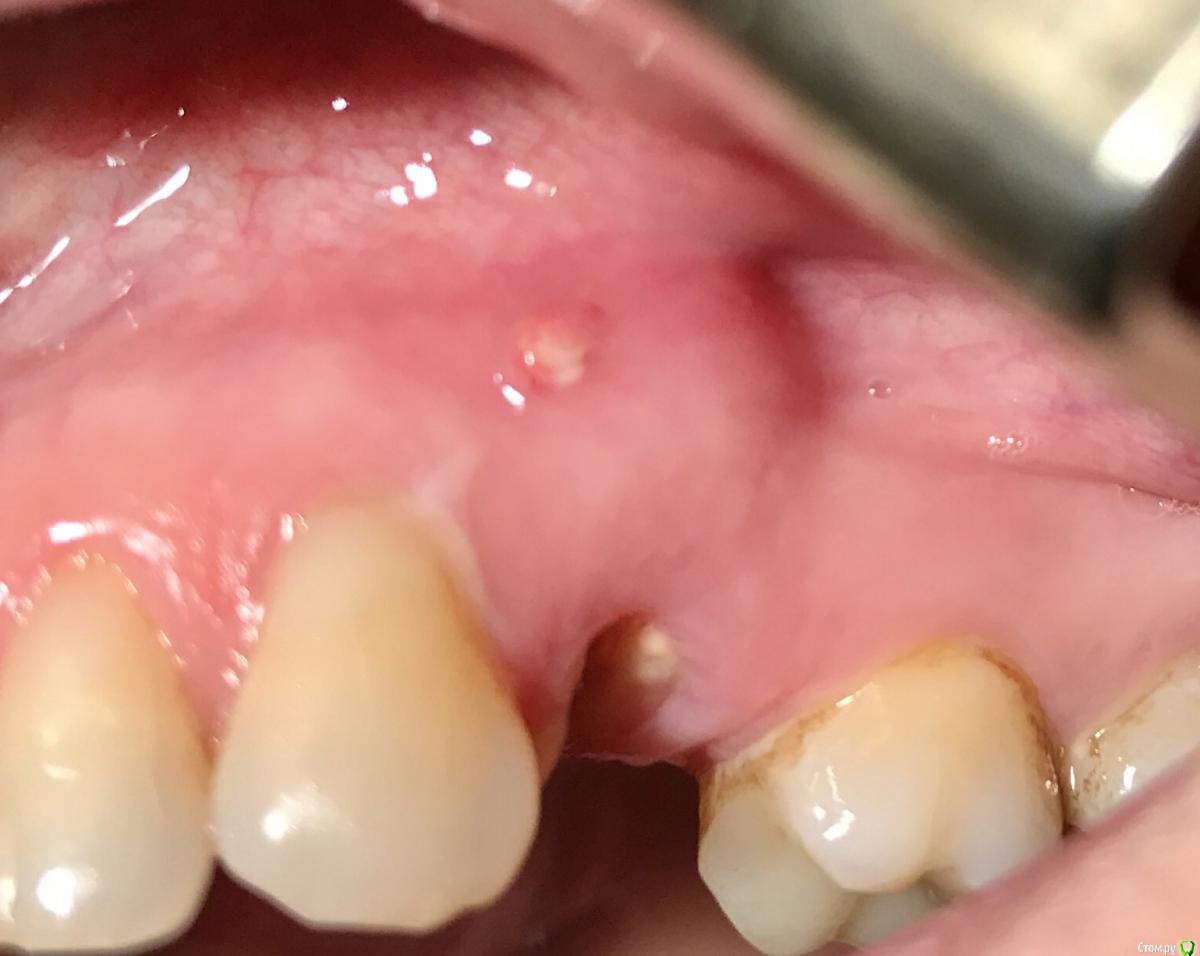

колесников Опубликовано 25 февраля, 2017 Поделиться Опубликовано 25 февраля, 2017 Здравствуйте коллеги! Представляю вашему вниманию этот клинический случай.В ноябре 2016 обратилась пациентка с жалобами на выпадение ортопедической конструкции в обл 24. Объективно: корни 24 не состоятельны. ,на десневом крае в проекции 24 свищевой ход с гнойным отделяемым.На КТ резорбция вестибулярной компактной пластинки и деструкция костной ткани в области щёчного корня.Приняв во внимание крайне негативное отношение пациентки к каким бы то ни было хирургическим вмешательствам и высоким эстетическим требованиям,было решено пойти на немедленную имплантацию .Снимки в день вмешательства,через 7,14 дней и 3мес.Имплант Astra tech profile 4.5х11мм. Сст с бугра вестибулярно. Вместо графта губки Коллапола (не вспомню причину,либо не было в наличии,либо отказ пациента). 15 Ссылка на комментарий

колесников Опубликовано 27 февраля, 2017 Автор Поделиться Опубликовано 27 февраля, 2017 Как обычно,хлоргексидином промываю. Ну это нас не испугаешь,а у большинства коллег Робустова в голове. И именно по-этому теперь иногда делаю фотопротокол. Менталитет у нас такой,на слово не верят. Ссылка на комментарий